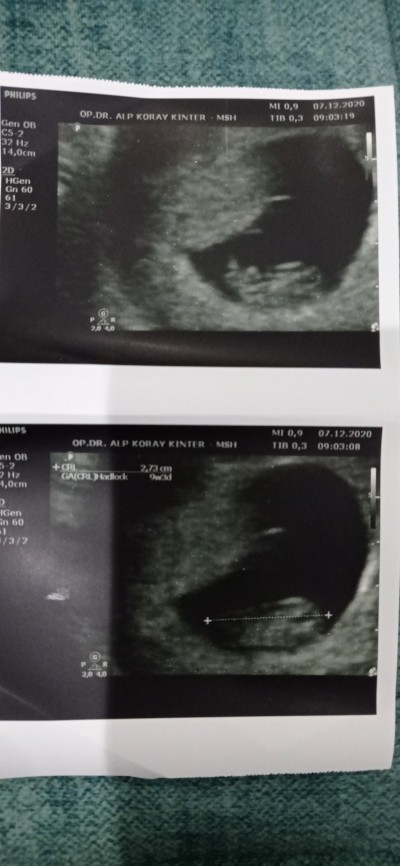

Ultrason kağıdından anlayan bakabilir mi

image

Gebelik haftası 20